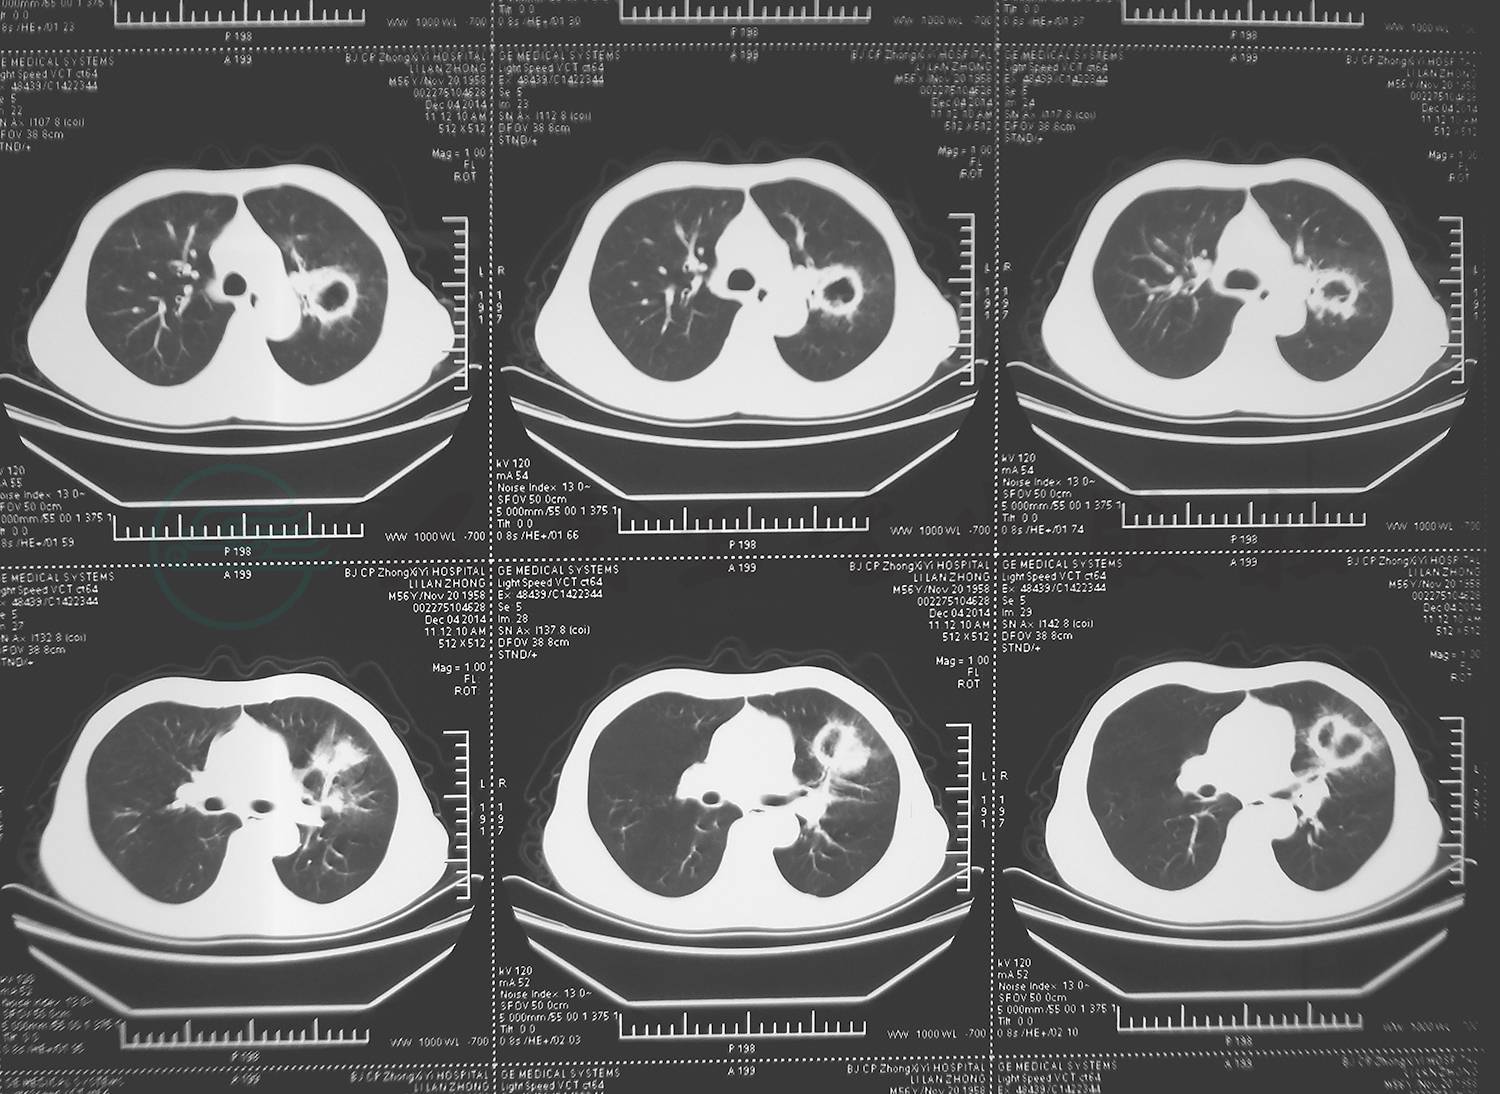

2014年12月18日(我院)胸部CT检查示:胸廓正常,右肺上叶可见小空洞影,未见液平,左肺可见多个厚壁空洞影,内无液平,双侧胸腔可见液体密度影,心包可见积液影(图1)。

图1 2014-12-18胸部CT